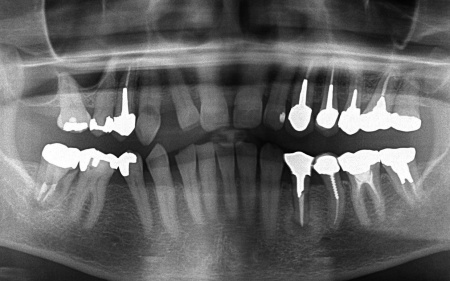

70代女性 歯根が割れた左下奥歯を抜きインプラントで噛み合わせを回復させた症例

抜歯後は骨や歯茎の回復を待ち、口腔内の状態が安定したことを確認して、インプラント埋入手術へ進みました。

後日、インプラントと骨がしっかりと結合したら、精密な型取りを行い、被せ物を作製します。

最後に完成した被せ物を装着し、痛みや違和感がないか、見た目や噛み合わせに問題がないかを確認して、治療を終了しました。